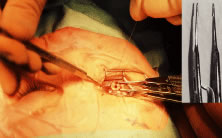

A muscle that moves from its desired location is called a slipped muscle.43–46 Causes of a slipped muscle include untying of the knot (Fig. 77A and B), inadvertent cutting of the suture, placing the suture too close to the insertion, or taking an inadequate bite of sclera with passage of the needle. In the latter case, the suture will “cheese wire,” or pull through the sclera. Finally, if the suture engages only the muscle capsule and not the tendon, the tendon can slide posterior within the muscle capsule. Because the maximal pull, or force, generated by an extraocular muscle is only 50 g, insufficient strength of the suture material is seldom the cause of a slipped muscle.

Fig. 77. A. This patient had a lateral rectus muscle recessed 5 days ago. The patient was referred for evaluation of overcorrection and poor abduction. The incision was explored, and the suture that was holding the rectus muscle had become untied. Careful examination of the blue suture under the conjunctiva raised suspicion of this complication. B. Schematic demonstrating the findings at surgical correction.